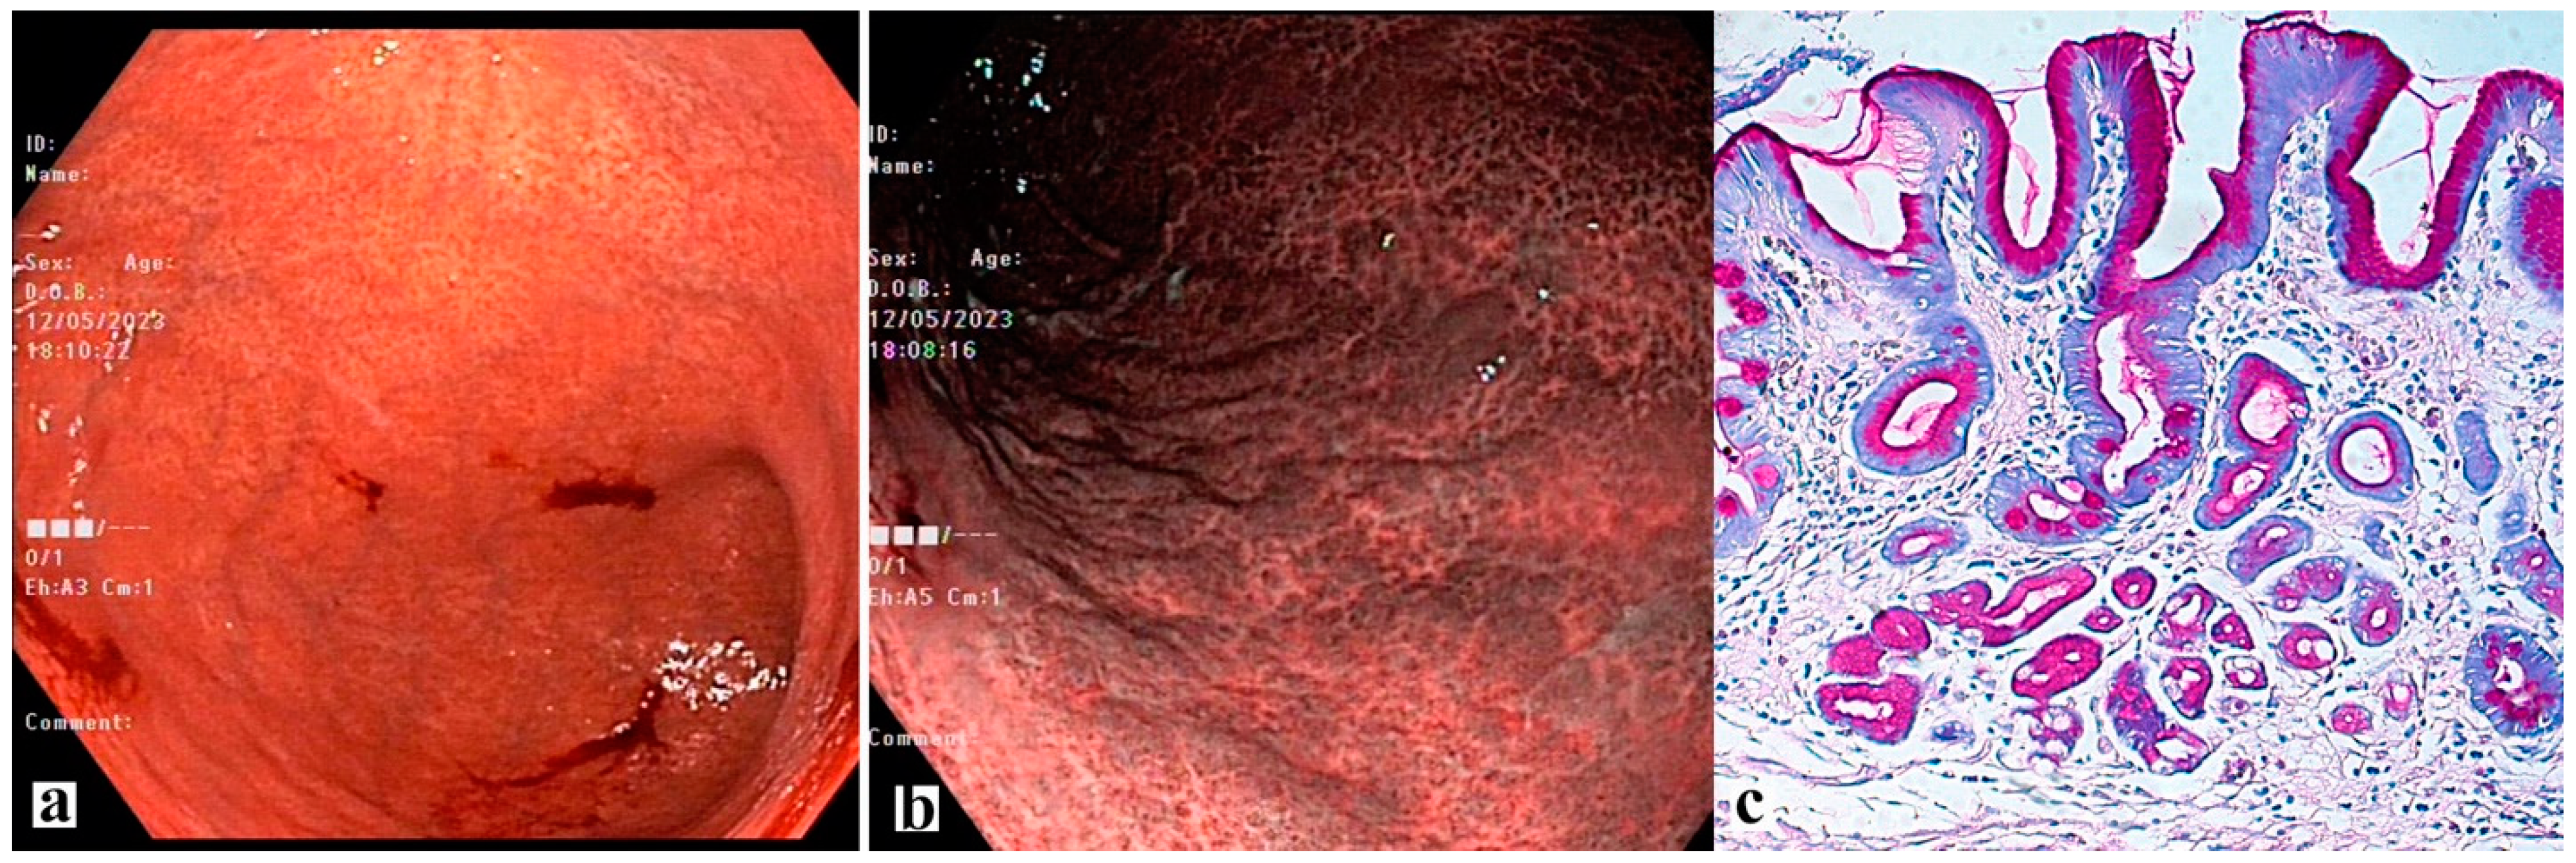

- Martins, B.C.; Moura, R.N.; Kum, A.S.T.; Matsubayashi, C.O.; Marques, S.B.; Safatle-Ribeiro, A.V. Endoscopic Imaging for the Diagnosis of Neoplastic and Pre-Neoplastic Conditions of the Stomach. Cancers 2023, 15, 2445. [Google Scholar] [CrossRef]

- Yagi, K.; Nakamura, A.; Sekine, A.; Graham, D. Features of the atrophic corpus mucosa in three cases of autoimmune gastritis revealed by magnifying endoscopy. Case Rep. Med. 2012, 2012, 368160. [Google Scholar] [CrossRef]

- Pimentel-Nunes, P.; Libânio, D.; Marcos-Pinto, R.; Areia, M.; Leja, M.; Esposito, G.; Garrido, M.; Kikuste, I.; Megraud, F.; Matysiak-Budnik, T.; et al. Management of epithelial precancerous conditions and lesions in the stomach (MAPS II): European Society of Gastrointestinal Endoscopy (ESGE), European Helicobacter and Microbiota Study Group (EHMSG), European Society of Pathology (ESP), and Sociedade Portuguesa de Endoscopia Digestiva (SPED) guideline update 2019. Endoscopy 2019, 51, 365–388. [Google Scholar]

- Zhang, Q.; Wang, F.; Chen, Z.Y.; Wang, Z.; Zhi, F.C.; Liu, S.D.; Bai, Y. Comparison of the diagnostic efficacy of white light endoscopy and magnifying endoscopy with narrow band imaging for early gastric cancer: A meta-analysis. Gastric Cancer 2016, 19, 543–552. [Google Scholar] [CrossRef] [PubMed]

- Pimentel-Nunes, P.; Libânio, D.; Lage, J.; Abrantes, D.; Coimbra, M.; Esposito, G.; Hormozdi, D.; Pepper, M.; Drasovean, S.; White, J.R.; et al. A multicenter prospective study of the real-time use of narrow-band imaging in the diagnosis of premalignant gastric conditions and lesions. Endoscopy 2016, 48, 723–730. [Google Scholar] [CrossRef] [PubMed]

- Kikuste, I.; Marques-Pereira, R.; Monteiro-Soares, M.; Pimentel-Nunes, P.; Areia, M.; Leja, M.; Dinis-Ribeiro, M. Systematic review of the diagnosis of gastric premalignant conditions and neoplasia with high-resolution endoscopic technologies. Scand. J. Gastroenterol. 2023, 48, 1108–1117. [Google Scholar] [CrossRef] [PubMed]

- Lee, J.W.; Lim, L.G.; Yeoh, K.G. Advanced endoscopic imaging in gastric neoplasia and preneoplasia. BMJ Open Gastroenterol. 2017, 4, e000105. [Google Scholar] [CrossRef]